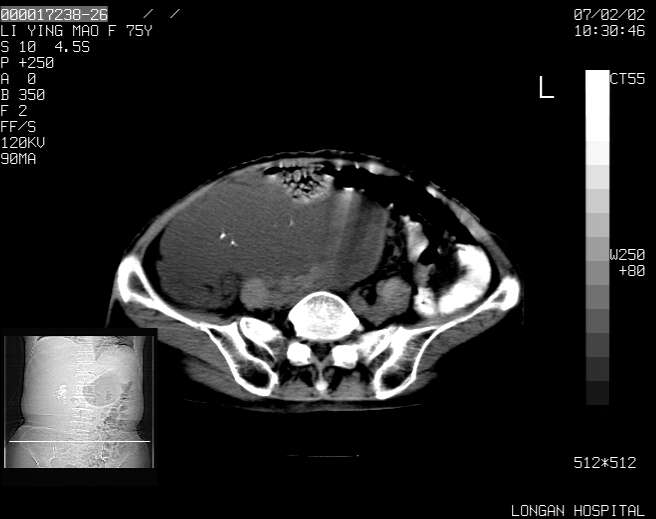

以下是引用dyqct在2007-2-10 8:53:00的发言:[br]考虑:1、肝脏多发囊肿[br] 2、左肾囊肿,右肾多发结石并积水。[br] 3、右胸少量积液。[br] 4、右肾周包裹性积液或淋巴管瘤(有见缝就钻的征象、薄隔、小结节状钙化)?[br] 5、腰椎动脉瘤样骨囊肿?[br] [br] [br]